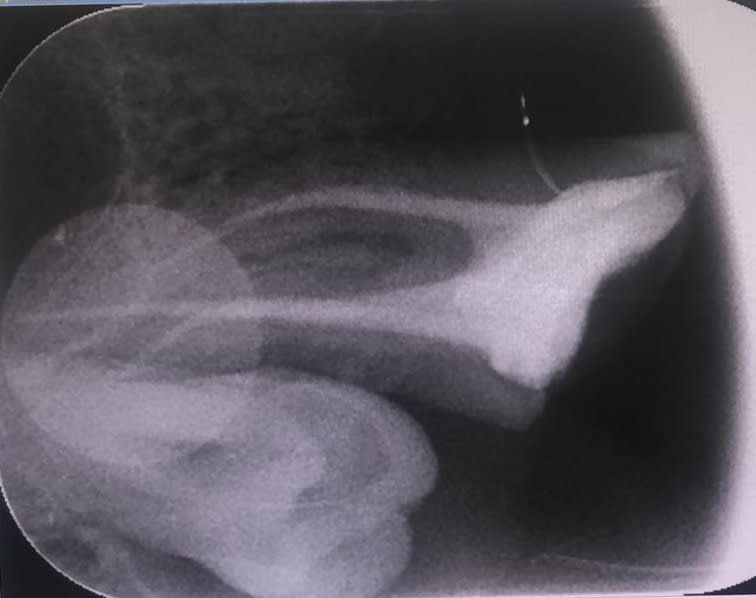

Patient vu il y a trois mois pour une dévitalisation de la 27 (cf radio) , vu deux mois plus tard, légère douleur à la percussion.

Pour moi l'endo à l'air convenable en terme de densité et de longueur….

4eme canal, présence de la sagesse incluse, radio apparemment OK mais mais mais....

canal supplémentaire en MV ou irritation du desmodonte de la 28 pr un dépassement d’hypochlorite ou de pâte. Un petit cone beam serait bienvenu

60% des 7 maxillaires ont un 4 ieme canal et 40% des échecs sont dus à des canaux " oubliés". Donc l'hypothèse la plus convaincante c'est le 4 âme canal. Pour la fêlure un sondage parodontal devrait pouvoir la mettre en évidence. Si tu as un endo de référence envoie lui ou au moins fait un CBCT.